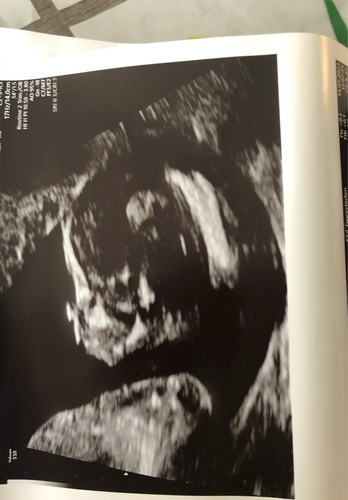

Op deze echo was ik 11+4 weken ☺️ ben benieuwd wat jullie denken te zien!

De kin is helaas niet op de foto’s te zien, maar misschien is het voorhoofd voldoende haha :)